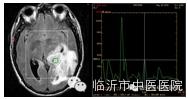

常用于超急性脑梗塞的诊断与鉴别诊断,有利于尽早挽救可逆性缺血性坏死脑组织,对于指导临床治疗具有重要的意义。

在脑肿瘤术前诊断,术前评估肿瘤特征,指导术者及术后评测肿瘤切除效果等方面有着广泛的临床应用价值。

磁共振波谱是分子成像技术,主要用于癫痫、肿瘤及梗塞的诊断与鉴别诊断。